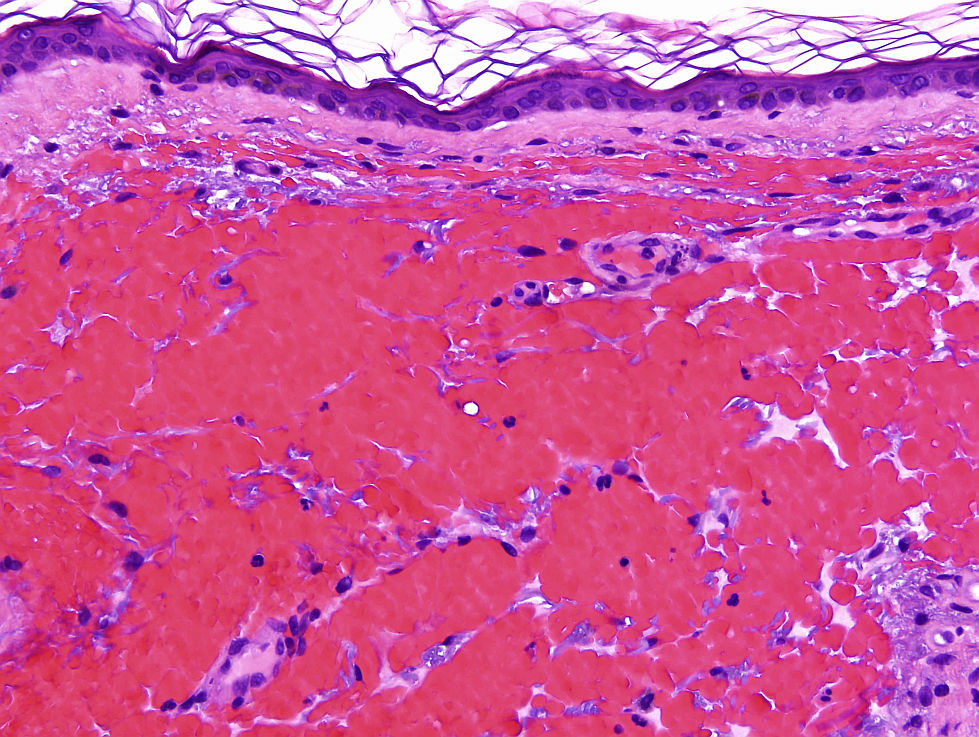

Cas dermatopatologia. Un cas adequat per a aquesta estació de l'any

Gener 2013

Podria suggerir-se el diagnòstic sense conèixer l'historial clínic?